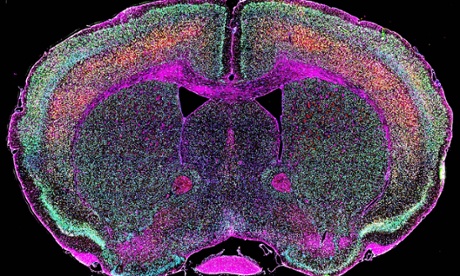

HERV-K expressed by large pyramidal neurons in layer 5 of the mouse cerebral cortex (stained yellow). Photograph: Nath Lab/ NINDS/ NIH

Expression of HERV-K genes alters the morphology of large pyramidal neurons in the mouse motor cortex (left). Photograph: Nath Lab/ NINDS/ NIH

Finally, the researchers created a strain of genetically engineered mice whose neurons express high levels of the env gene. Behavioural tests revealed that these animals developed impairments in motor function. They had difficulty walking and balancing compared to healthy mice, and these symptoms progressed rapidly between 3 and 6 months of age, killing half of the animals by 10 months of age.

Closer examination revealed that neurons in the motor cortex displayed various structural changes associated with degeneration, such as a decrease in the length, branching and complexity of dendrites, and a reduction in the number of dendritic spines, the tiny, finger-like protuberances which receive chemical signals from other cells.